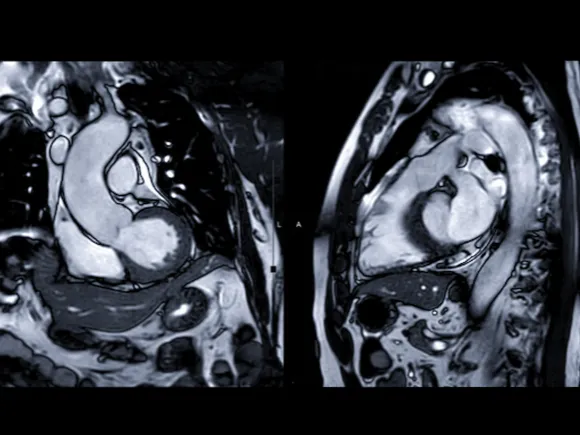

A cardiac magnetic resonance image (MRI), sometimes abbreviated as CMR, is a non-invasive imaging test that uses magnetic fields and radio waves to create images of the heart.

This test helps evaluate the squeezing capacity of the heart and the presence of valvular abnormalities, congenital cardiac abnormalities, scarring within the muscular tissue of the heart or abnormal protein deposition in the tissue of the heart.